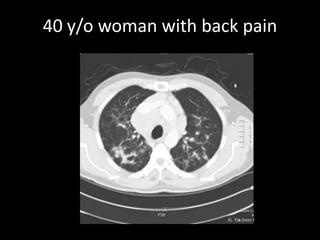

A 52-year-old man underwent a CT FDG PET fused PET/CT scan for a palpable lump. A 40-year-old woman with back pain received MRI scans including STIR, T1, and contrast images. Another patient, a 75-year-old woman with osteoporosis, also received imaging.